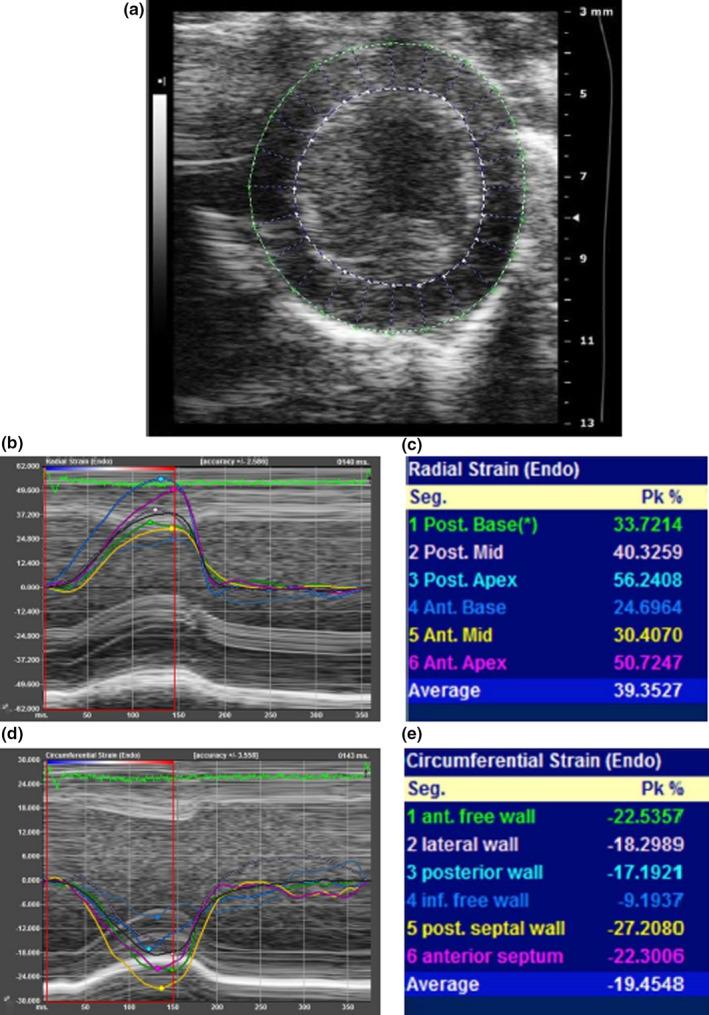

A total of 135 female Syrian hamsters were anesthetized and studied with a small animal dedicated echocardiography system. Echocardiography measurements were obtained from M-mode and B-mode images. Feasibility and 95% reference intervals were obtained for LVEF using three different approaches: LVEF_Teichholz (from M-mode linear measurements), LVEF_BMode (from area-length method), and LVEF_ STE (from strain), and for global longitudinal (GLS), circumferential (GCS), and radial (GRS) endocardial strain. Reproducibility was assessed as intra-class correlation coefficients.

RESULTS

Feasibility of LVEF and endocardial strain was high (95% in FEVE_Teichholz, 93% in the LVEF_BMode, 84% in the LVEF_STE, 84% from PSLAX, and 80% from PSSAX). Values of LVEF_Teichholz were significantly higher than values of LVEF_BMode, and LVEF_STE-derived methods (59.0 ± 5.8, 53.8 ± 4.7, 46.3 ± 5.7, p < 0.0001). The 95% reference intervals for GLS, GCS, and GRS were respectively -13.6(-7.5;-20.4)%, -20.5 ± 3.1%, and + 34,7 ± 7.0%. Intra-class correlation coefficients were 0.49 - 0.91 for LVEF measurements, 0.73 - 0.92 for STE, with better results for LVEF_Teichholz and GLS.